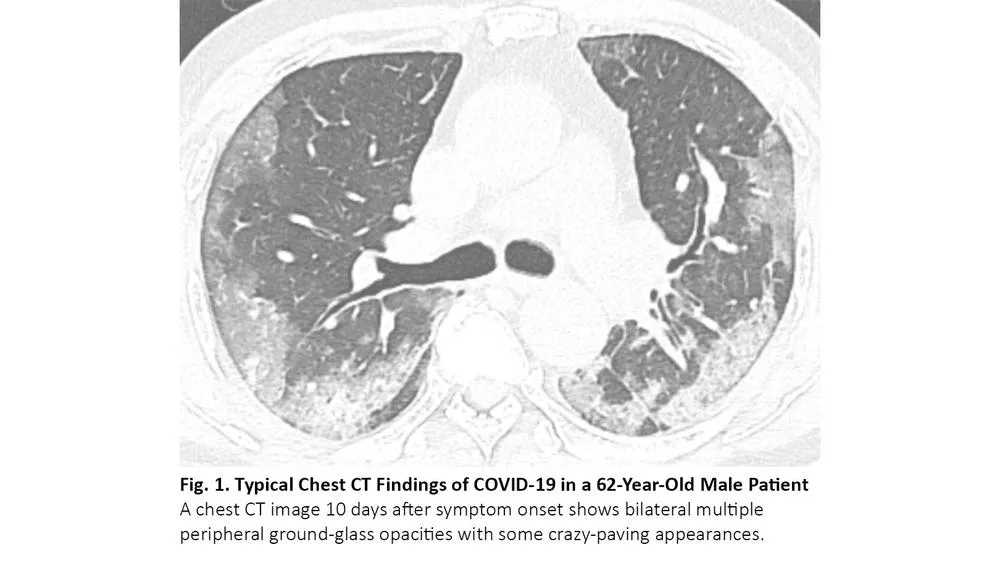

COVID-19患者的肺部CT的典型表现为双侧多发磨玻璃样影,好发于肺周3(图1)。61%~72%的COVID-19患者在症状出现后1周左右有典型CT表现,而非COVID-19患者只有不到10%人群有此类表现。4,5

图1. COVID-19患者胸部CT的典型表现